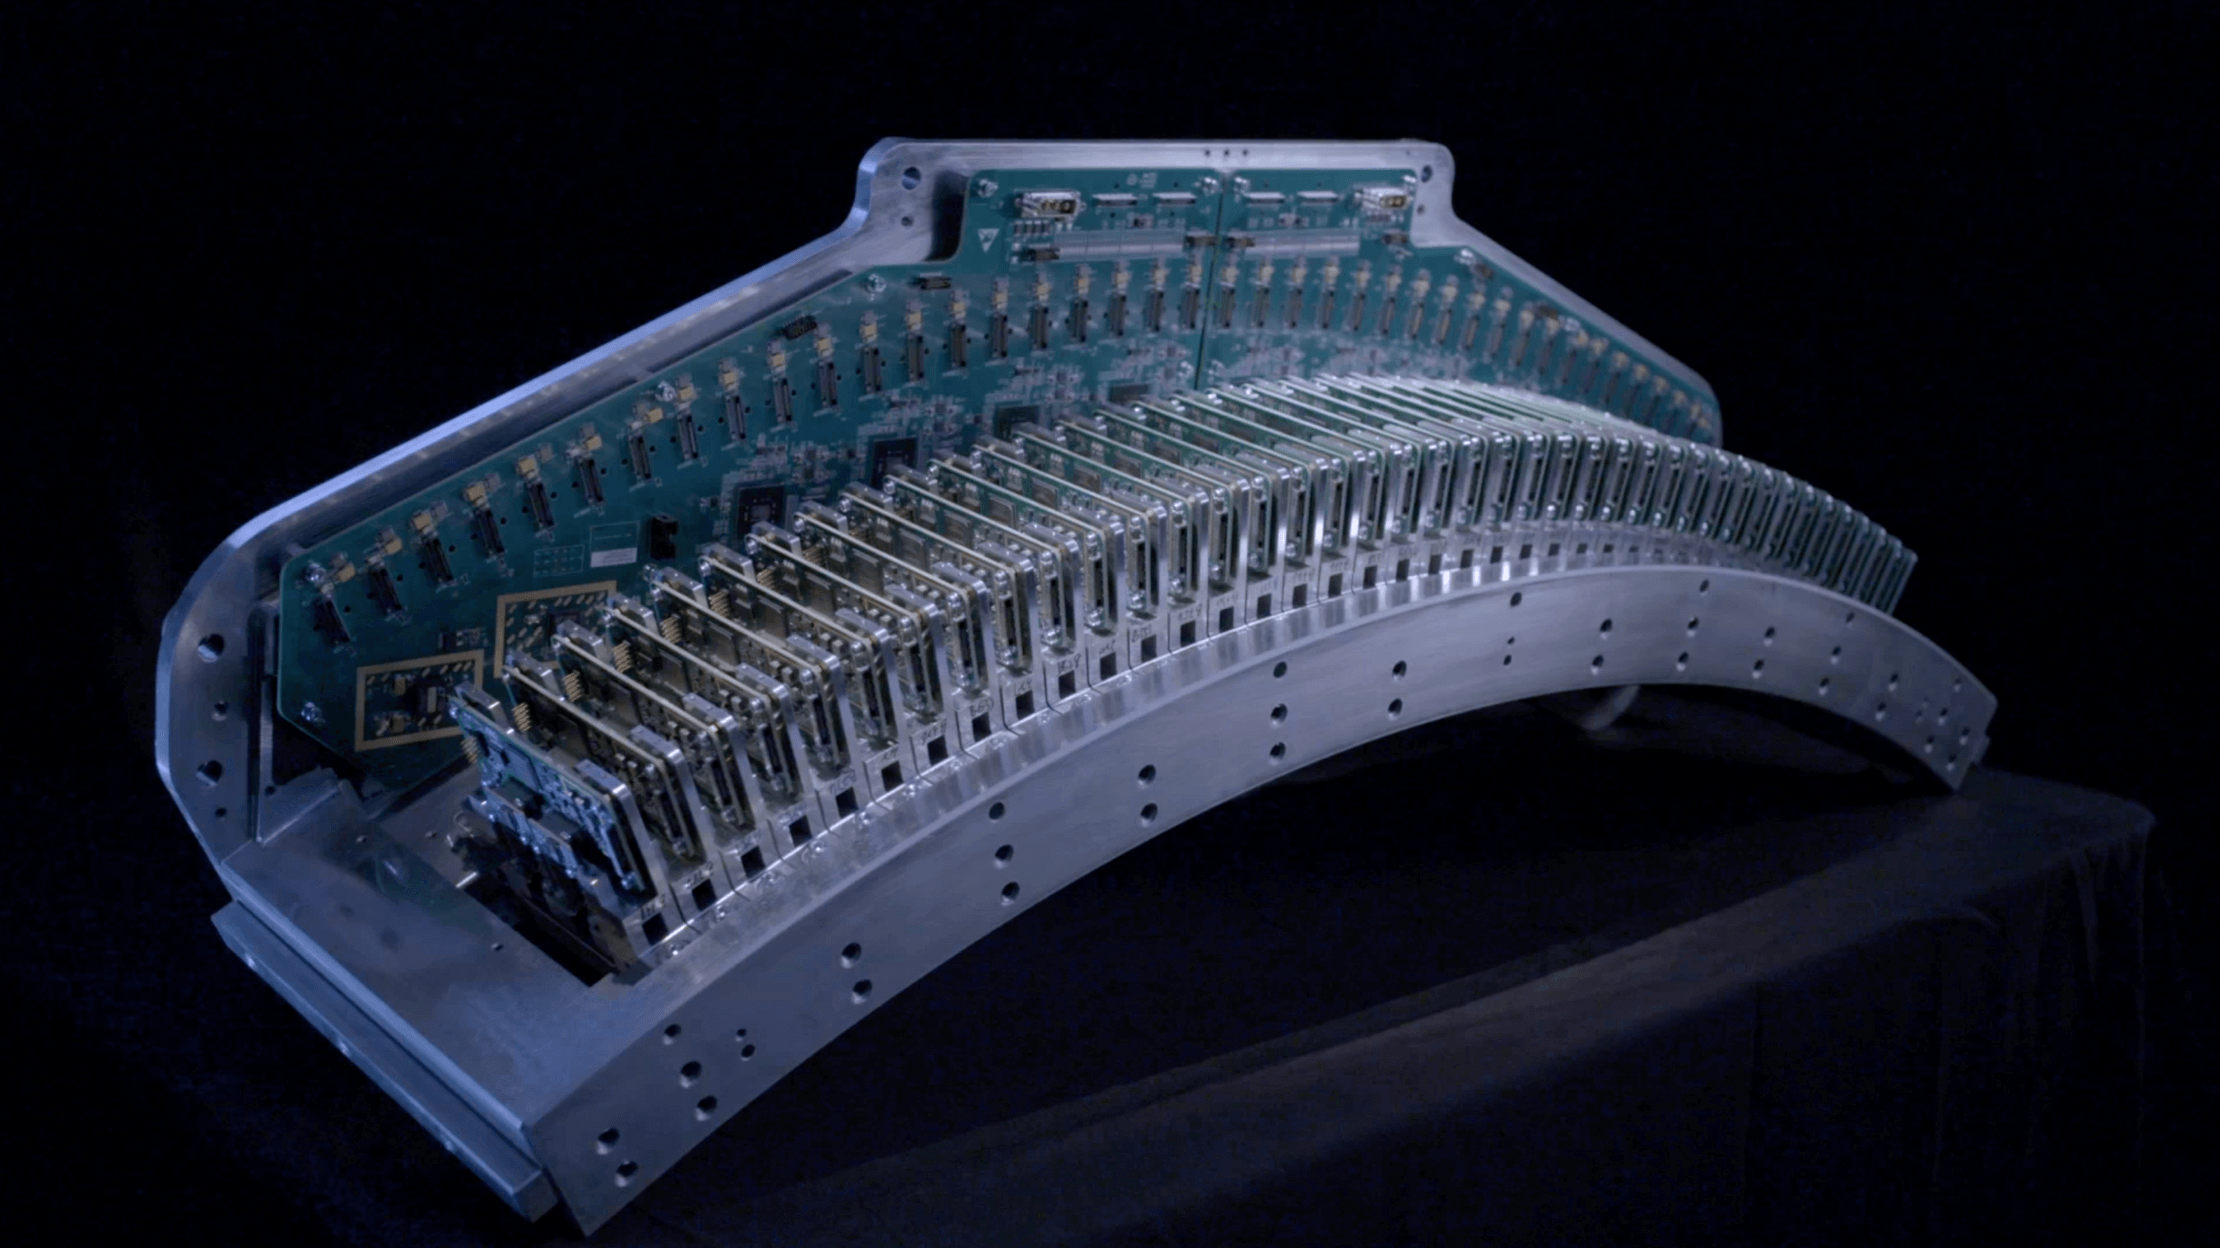

超高密度体素,实现海量原始数据采集,从数据源头提升成像质量,精微显示细小结构

以高速稀土陶瓷材料打造闪烁晶体,大幅提高X射线转换效率与响应速度

基于高度集成化设计,直接输出数字信号,实现降噪、低辐射剂量与高图像质量兼而得之

提高X-Y平面空间分辨率,内耳、小关节、肺部等微小细节纤毫毕现

专业算法降低伪影,优化金属植入物与周围组织的对比

突破0.5mm层厚的精细图像,精微显示细小结构